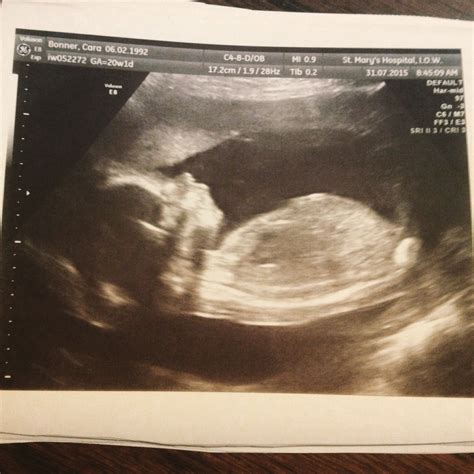

Another example of what you might see during your 20 week ultrasound. The scan captures various aspects of the baby's development, including the heart, brain, kidneys, and spine.

This image shows the baby's head circumference, abdominal circumference, and femur length, which are key measurements used to assess development and growth.